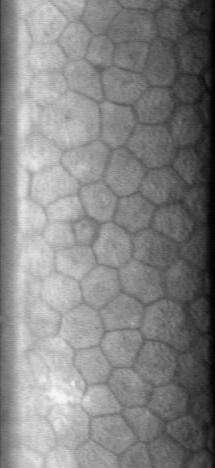

The normal corneal endothelium is a single layer of uniformly sized cells with a predominantly hexagonal shape. This honeycomb tiling scheme yields the greatest efficiency, in terms of total perimeter, of packing the posterior corneal surface with cells of a given area. The corneal endothelium is attached to the rest of the cornea through Descemet's membrane, which is an acellular layer composed mostly of collagen.